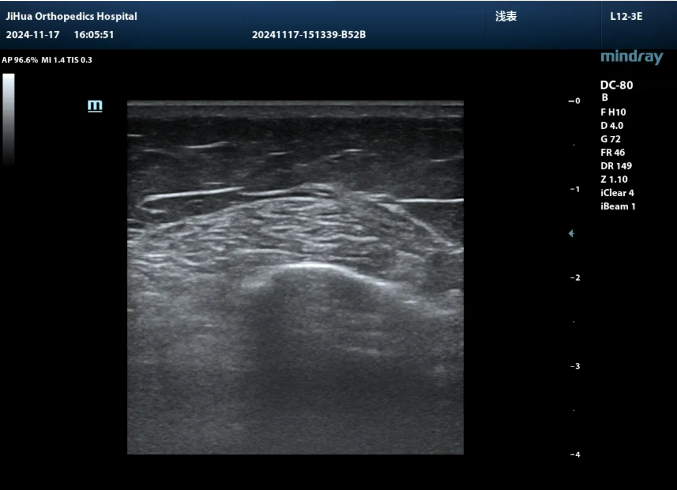

濟(jì)華骨科彩超室高清設(shè)備